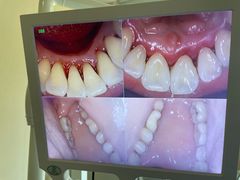

• 优伢仕口腔(汽车西站店)

• -优伢仕口腔(汽车西站店)

小丝 | 24-04-09